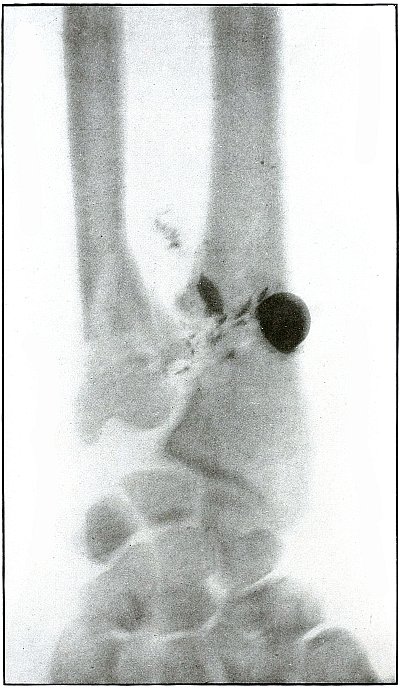

Plate 65.

_

[Pg 141]

Rifle—Plate 65.

LOWER EXTREMITY.

Gunshot Fracture of the Tibia.

The course of the bullet was transverse, from within outward, striking the bone near the outer border with the velocity of mid or long range, producing long fissures without separation of fragments.

The safety pin, of course, lies in the dressings and on the side away from the plate, as shown by its somewhat indefinite outline and increased length.

The wounds of entrance and exit are practically the same.

The treatment in such cases is that of a simple fracture, except for the management of an occasional infection, and the results are favorable. [Pg 142]